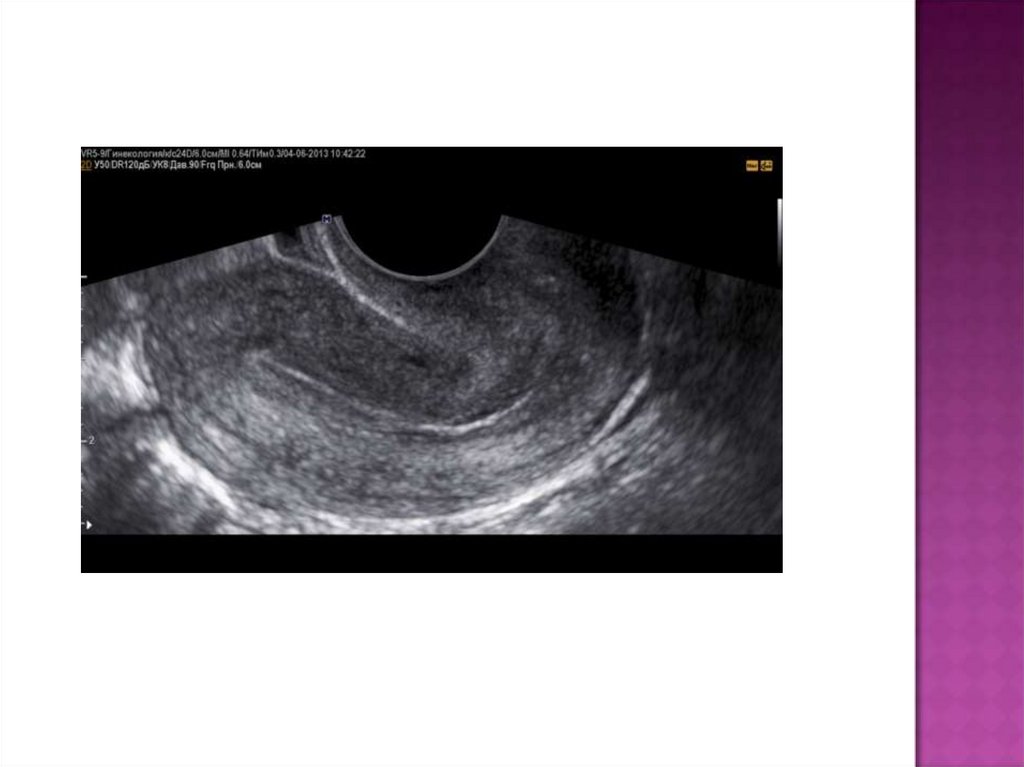

УЗИ:

УЗИ позволяет заподозрить данное заболевание по

сочетанию признаков:

·субинволюция матки;

·расширенная полость матки со множеством точечных

эхопозитивных включений (пузырьки газа);

·выраженный гипоэхогенный контур полости матки

(инфильтрация).

С помощью УЗИ можно обнаружить фрагменты последа

(эхопозитивные наложения на стенках матки).